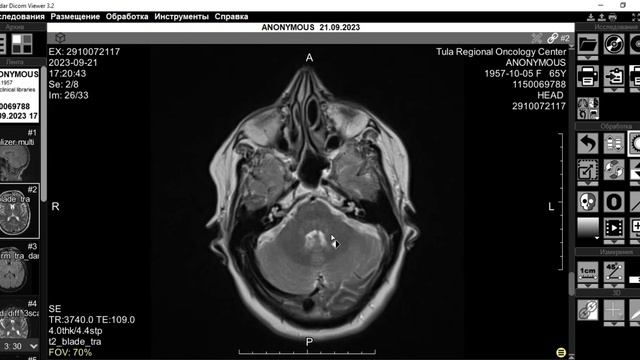

прямой эфир с Романом Вадимовичем Бартеневым @orthodoc.md - врачом ультразвуковой диагностики, ортопедом-травматологом, мануальным терапевтом, специалистом по скелетно-мышечной боли и физической реабилитации. Тема прямого эфира: «МРТ. Зачем это исследование?» Руководитель проекта - Касаткин М.С. @dr.kasatkin вместе с нашим гостем обсудит следующие вопросы: какой смысл МРТ в современном мире; нужно ли знать МРТ массажисту и тренеру; все ли врачи понимают МРТ; МИФЫ об МРТ. https://www.instagram.com/kineziocourse/ КИНЕЗИОТЕЙПИРОВАНИЕ ОБУЧЕНИЕ https://www.instagram.com/orthodoc.md/ Бартенев Роман Вадимович ОРТОПЕД, МАНУАЛЬНЫЙ ТЕРАПЕВТ https://kinesiocourse.getcourse.ru/mri ОНЛАЙН КУРС МРТ КОЛЕННОГО СУСТАВА